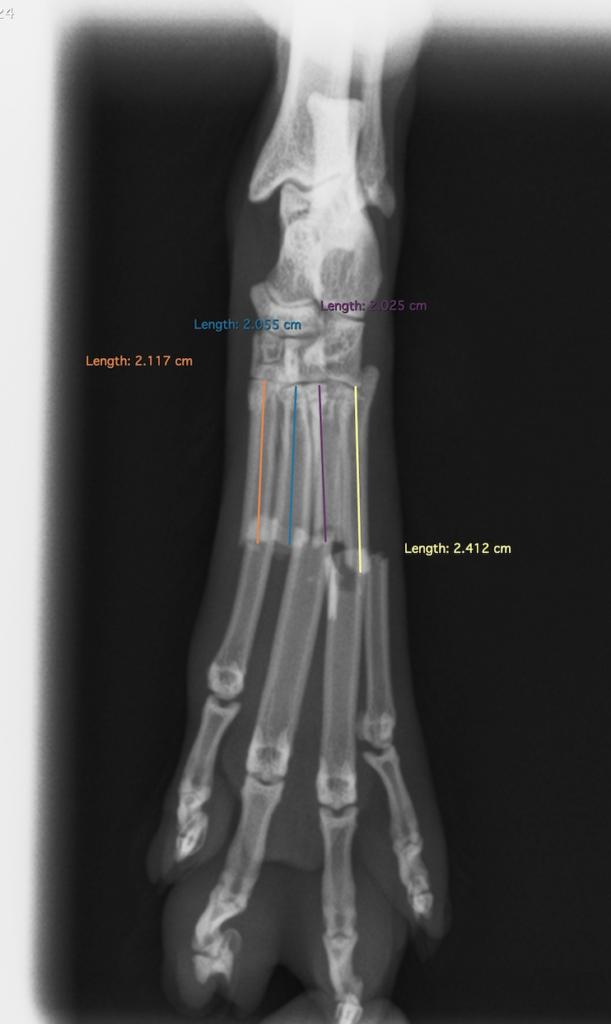

【X線検査所見】

第2,3,4,5,中足骨骨幹部の横骨折とそれに伴う軟部組織の腫脹が認められる。